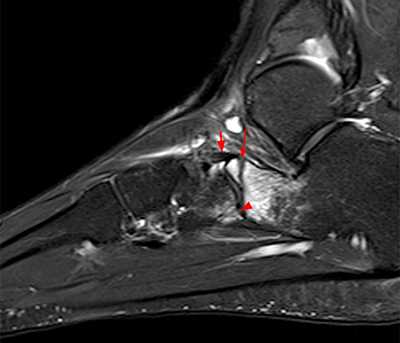

Рентгенологическое исследование

Для диагностики повреждения сустава Шопара делают рентген, КТ и МРТ. На передне-задней рентгенограмме определяют величину пяточно-кубовидного угла. Проводят одну касательную к наружному краю кубовидной кости и вторую касательную к наружному краю пяточной кости. В норме угол между касательными колеблется в пределах от 0 до 5°. Увеличение угла свидетельствует о нарушении стабильности пяточно-кубовидного сочленения. КТ во фронтальной и сагиттальной плоскостях позволяет выявить дефект суставных фасеток, смещение костей при вывихе и фрагментацию костей при переломе. КТ, по сравнению с рентгенографией, является более информативным методом диагностики. МРТ позволяет выявить дефекты отдельных связок.

Рис. 7. Перелом кубовидной кости по передней поверхности

Рис. 8. Переломо-вывих в суставе Шопара